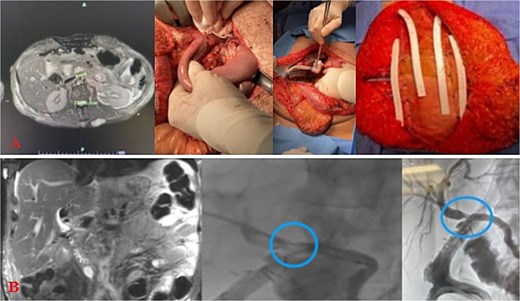

Massive transfusion protocol was initiated, and he was taken to the operating room for an emergent exploratory celiotomy. Upon entrance into the abdominal cavity, a 10 cm hematoma, along the transverse colon consistent with a mesenteric arterial hemorrhage, was identified and rapidly controlled (Fig. 1A). A Cattell-Braasch maneuver was employed, mobilizing the right colon, and a Kocher maneuver to fully explore the duodenum, revealing a AAST Grade II D2 injury that was repaired in 2 layers (Fig. 1B). The pancreatic head and tail had AAST Grade II injuries with multiple arterial bleeds that were controlled with suture ligation and argon beam coagulation (Fig. 1C).

Index operation. A: Transverse colon hematoma. B: Duodenal (D2) injury. C: Pancreatic head and tail vascular injury. D: Common bile duct and intraoperative cholangiogram through the common bile duct and cystic duct.

On initial inspection, the GB infundibulum was contused, and there was bile staining along the porta hepatis. The common bile duct (CBD) was identified and appeared grossly normal. However, due to the proximity of the pancreatic head injury and bile staining, we performed an intraoperative cholangiogram (IOC) through a mid-portion CBD needle ductotomy, to spare the GB as a potential conduit if a biliary repair was required. The initial IOC did not reveal an injury to the CBD and did not demonstrate extravasation of contrast (Fig. 1D). The needle ductotomy was closed with a running 3–0 Monocryl stitch. As we were concluding the damage control laparotomy a persistent, mild, bile staining within and along the porta hepatis, was noted. The possibility of a more proximal extrahepatic bile duct injury was raised as the common bile needle ductotomy closure remained intact.

Further inspection of the GB and proximal extra biliary ductal system revealed a large GB bed hematoma and partial avulsion of the GB (AAST Grade 3). Due to the risk of delayed GB ischemia, a cholecystectomy, and an additional IOC via the cystic duct this time was performed to rule out a more proximal ductal injury and a possible bile leak from the prior IOC distal needle ductotomy. The more proximal and distal IOC did not reveal a bile leak, however, the more proximal ductal structures were not optimally demonstrated. No further bile staining was noted. The abdomen was irrigated, and 4 Jackson-Pratt (JP) drains and an AbThera™ Advance Open Abdomen Dressing (3 M, Saint Paul, MN, USA) were placed. The patient was stabilized and transferred to the intensive care unit (ICU) for further resuscitation, on triple antibiotics, pantoprazole, and a somatostatin drip.